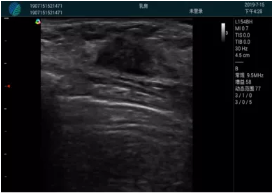

頸動(dòng)脈血流充盈飽滿,無(wú)外溢

肝內(nèi)血管顯示清晰,血流敏感無(wú)外溢